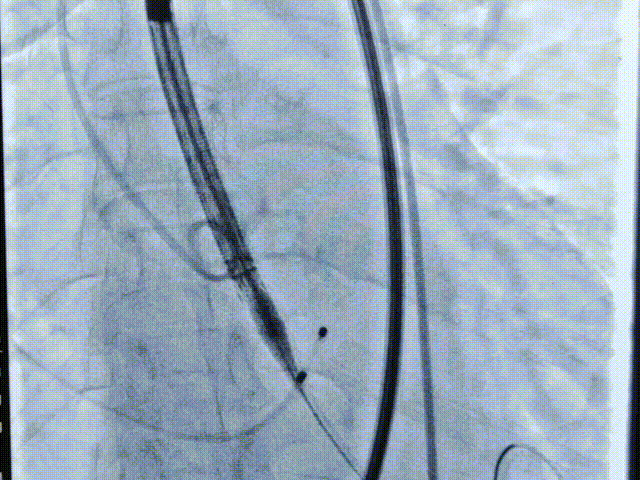

术中影像

主动脉根部造影

术中多次室颤,故当机立断,不进行预扩,直接植入L26号的VenusA-Valve瓣膜。

起始释放

第一次释放

位置稍深,选择回收,重新定位释放